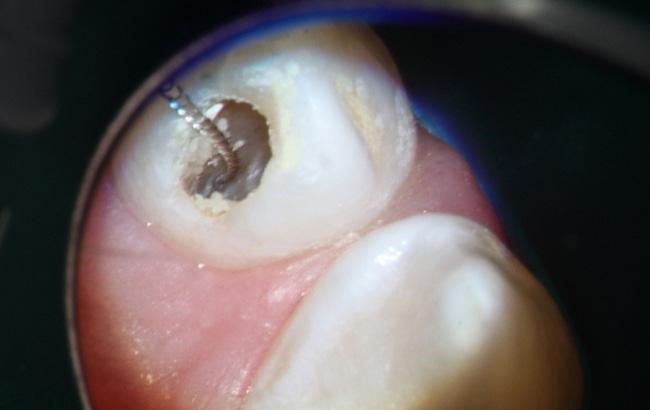

Dens Invaginatus (DI), a relatively uncommon developmental dental anomaly characterized by the invagination of enamel and dentin into the tooth structure, particularly the Type III variant which extends beyond the cementoenamel junction and possesses its own independent apical foramen, presents intricate endodontic challenges stemming from its often highly complex and unpredictable internal anatomy. Successful management requires a meticulous and tailored approach. This case report details the successful non-surgical root canal treatment of a Type III DI in a 15-year-old male's maxillary lateral incisor (tooth 12) with a pulpless, infected root canal system and a chronic apical abscess attributed to the DI defect. Preoperative evaluation involved clinical examination and periapical radiographs. While cone-beam computed tomography (CBCT) offers detailed visualization of such anomalies, its use was avoided to minimize radiation in this young patient. Clinical findings and conventional radiographs were deemed sufficient for treatment planning.

The endodontic therapy was conducted over four appointments. Access cavities were precisely prepared for both the main canal and the invagination, guided by a dental operating microscope. Working lengths were determined electronically and confirmed radiographically. The main canal was shaped using rotary files. The narrow, irregular invagination was meticulously instrumented with hand files, utilizing both EDTAC and copious sodium hypochlorite irrigation for thorough cleaning and disinfection. Calcium hydroxide mixed with Ledermix was used as the initial intracanal medicament to address infection and inflammation.

The fourth appointment involved re-access, final EDTA irrigation, and obturation. The main canal was obturated with a single gutta-percha cone and AH-26 Cement. Due to the invagination's complex morphology, a thermoplasticized injectable gutta-percha system ensured complete three-dimensional filling of this aberrant space. The access cavity was then permanently restored with composite resin to prevent microleakage.

A six-month clinical and radiographic follow-up demonstrated a successful outcome. The patient was asymptomatic with no tenderness, and the previously present sinus tract had resolved. Radiographic evaluation revealed a significant reduction in the periapical radiolucency, indicating healing of the chronic apical abscess.

In conclusion, this case underscores the critical role of meticulous chemomechanical preparation of both the main and invaginated canal systems, the strategic use of appropriate intracanal medicaments, and the application of tailored obturation techniques, such as thermoplasticized gutta-percha for complex anatomies, in achieving successful endodontic outcomes in challenging DI cases. While CBCT is a valuable diagnostic tool, this case highlights that thorough clinical assessment combined with carefully interpreted conventional radiographs can be sufficient for diagnosis and treatment planning in younger patients. Ultimately, a strong foundation in basic endodontic principles and the ability to adapt treatment strategies to the unique anatomical complexities of Dens Invaginatus remain paramount for successful management.

X-ray 1: A large periapical radiolucency in association with tooth #12, with a gutta-percha point tracing through the visible sinus tract originating from this area.

X-Ray 5: The six-month follow-up radiograph demonstrates a significant decrease in the dimensions of the radiolucent area, consistent with a favourable outcome of the endodontic treatment.